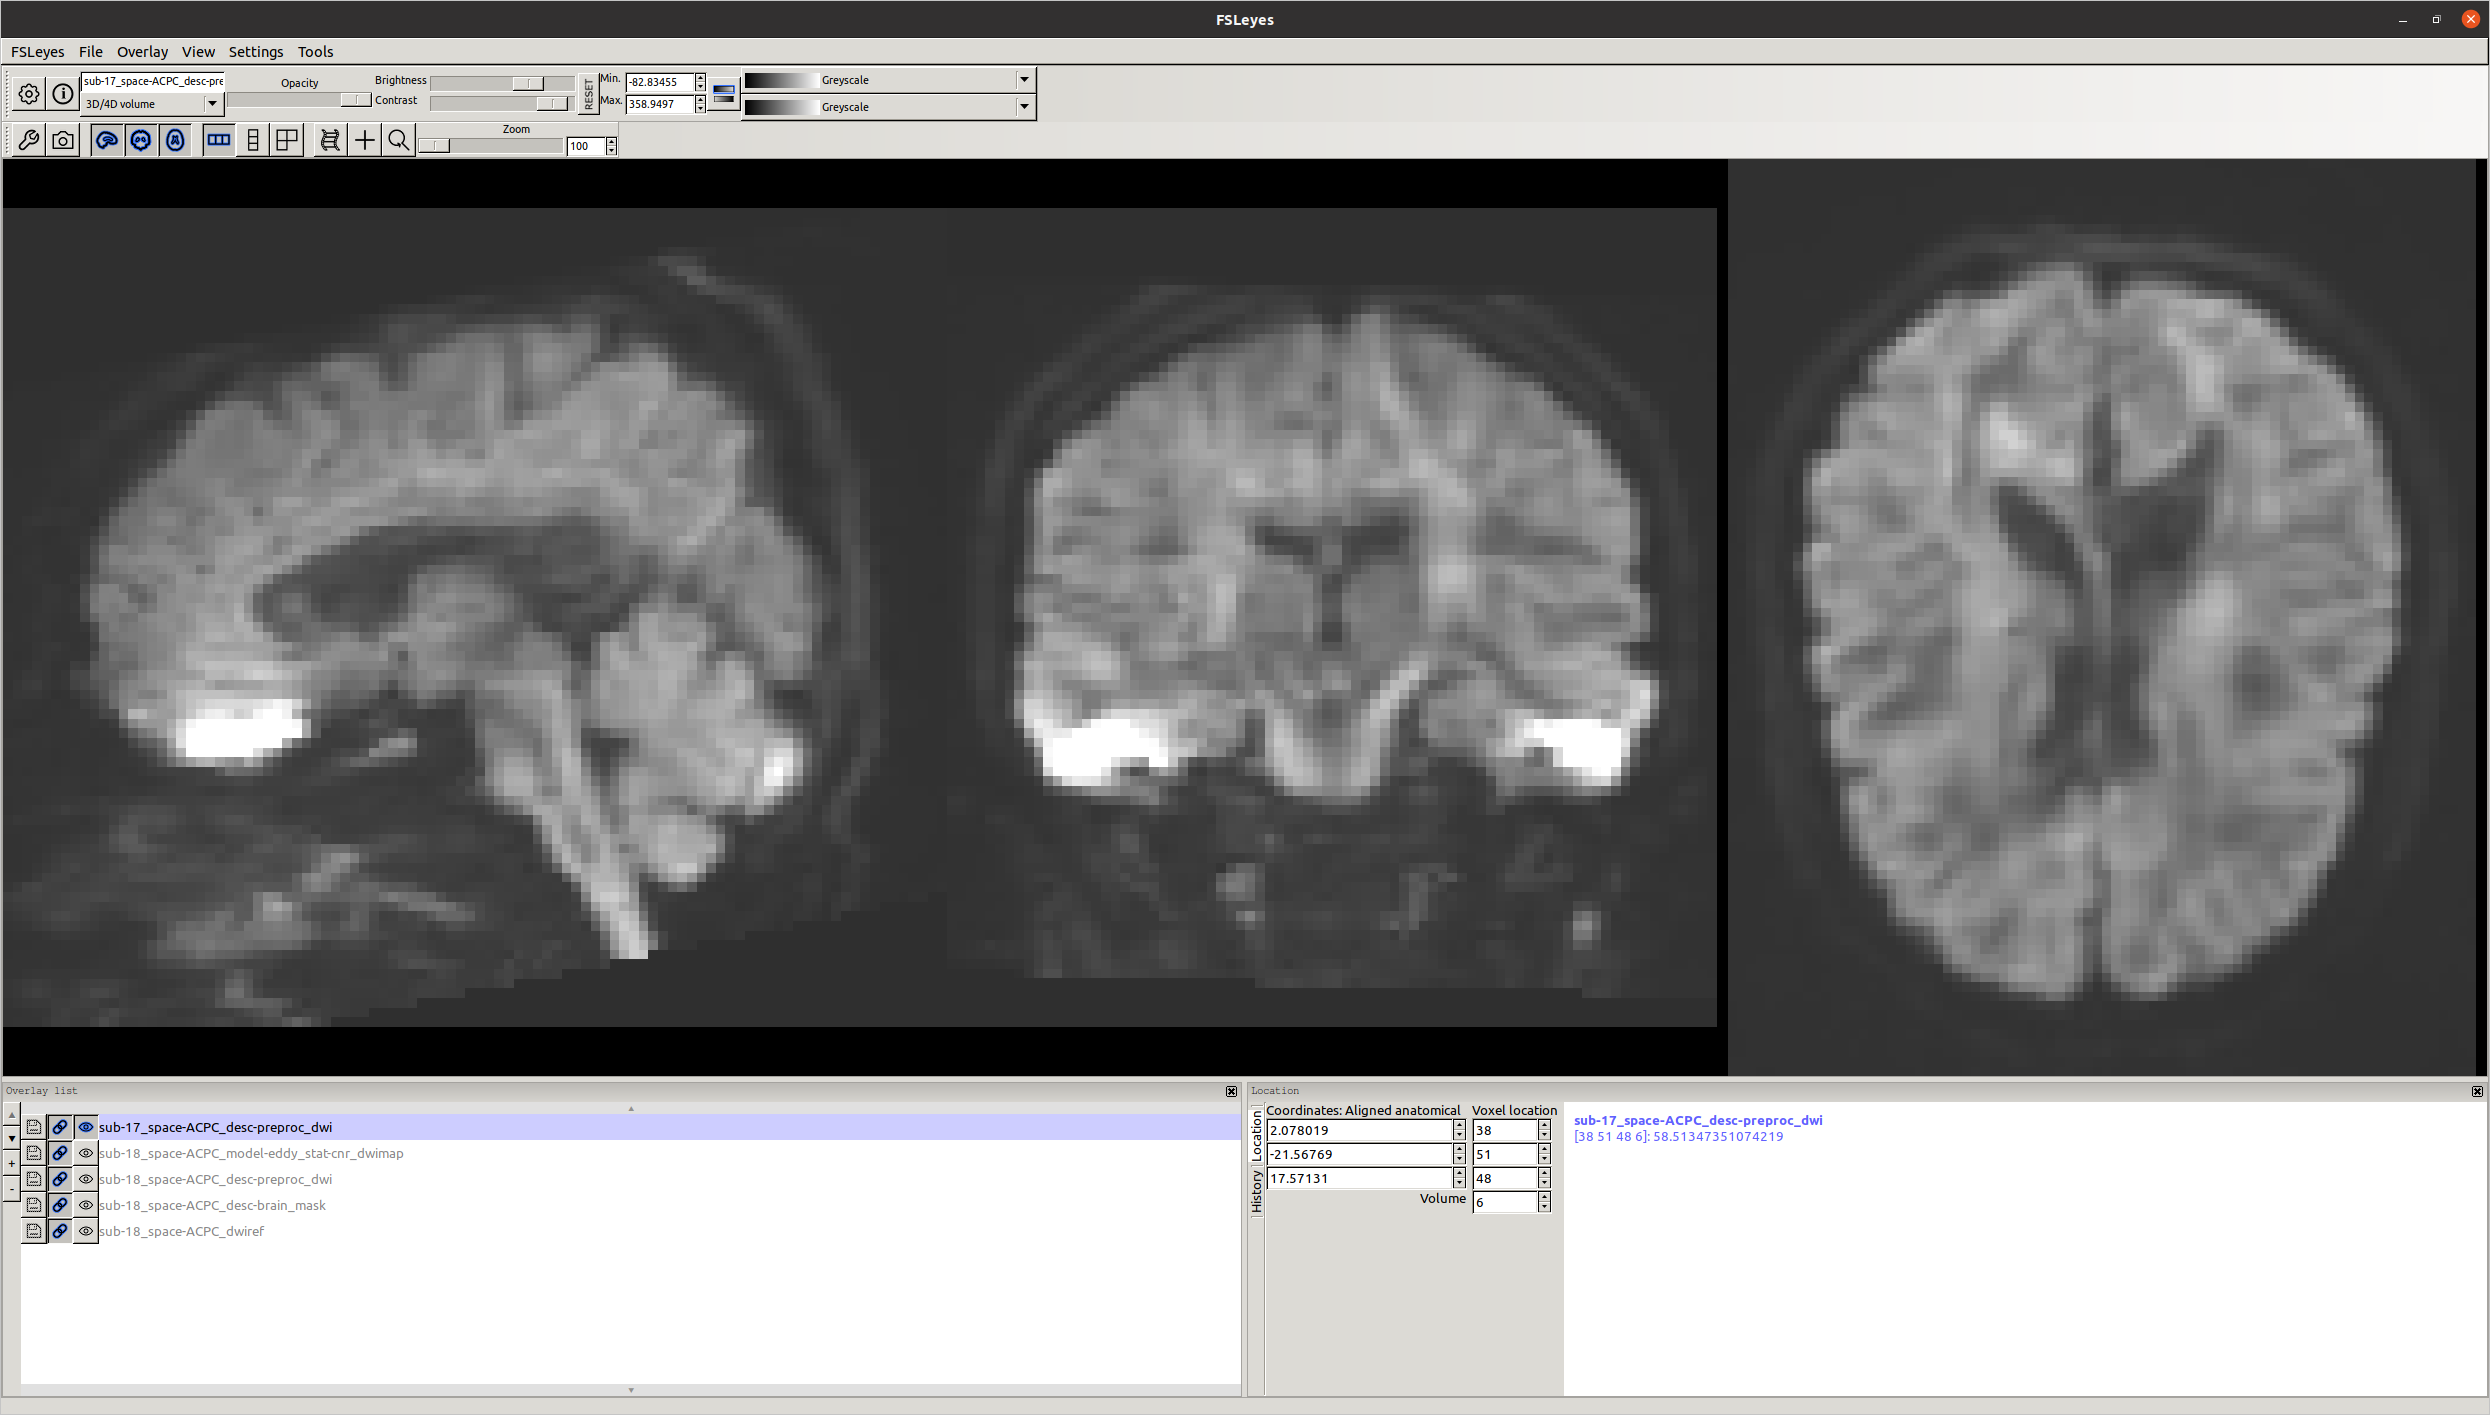

Concerning the hyperintensities, I do use field maps. Here is a screenshot of the output:

The hyper intensities do not look ideal, but are those regions important for your study hypotheses?

I’ve seen this kind of signal pileup in bipolar schemes before. I don’t think there’s much you can do about it unfortunately